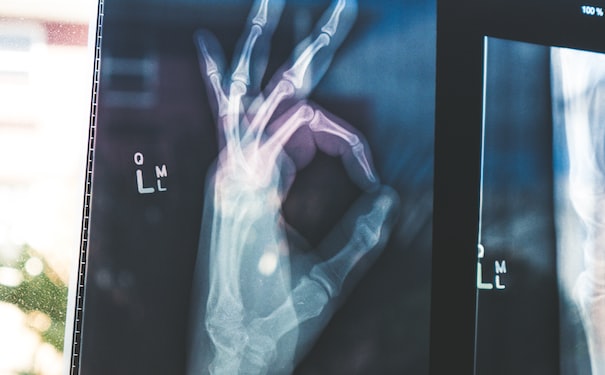

"利用環(huán)保醫(yī)學(xué)模型進(jìn)行可視化診斷!"

環(huán)保醫(yī)學(xué)模型為醫(yī)生提供了一種直觀的方式來進(jìn)行診斷。通過使用模型,醫(yī)生可以更清楚地了解患者的病情,幫助他們做出準(zhǔn)確的診斷和制定有效的治療方案。